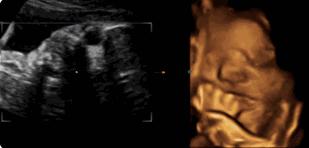

【在妇产科医院,你可以看到这样的胎宝】

麻麻,我在咬手指哟!